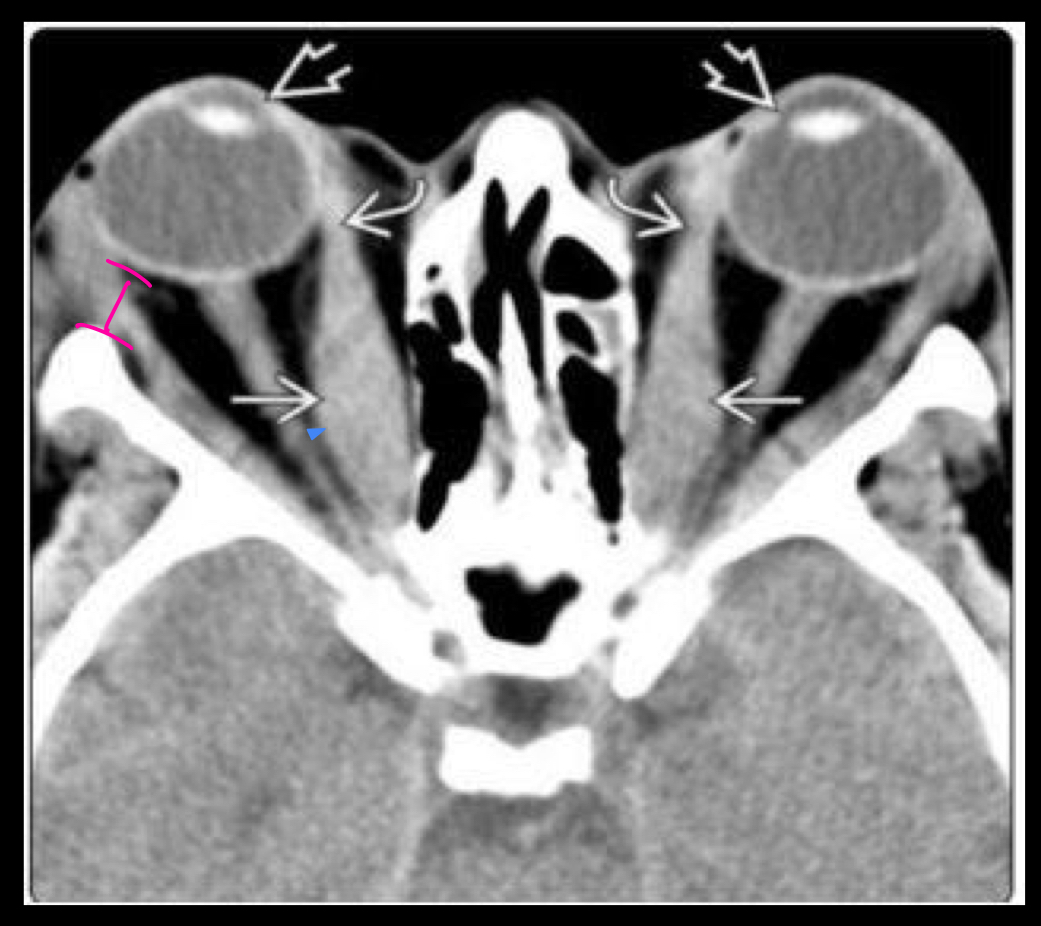

Que es?

A

TC ORBITOPATIA TIROIDEA

* Agrandamiento de los musculos extraoculares

* Exoftalmos

* nervio optico estirado

Tc EXOFTALMOS

* protusion ocular anormal

* disociasion indice globo ocular-linea zigomatica

* Masa Ocupativas retrooculares